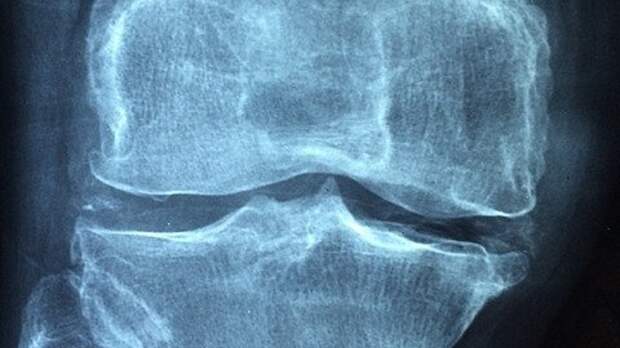

Болезни могут поджидать вас почти что на каждом шагу.